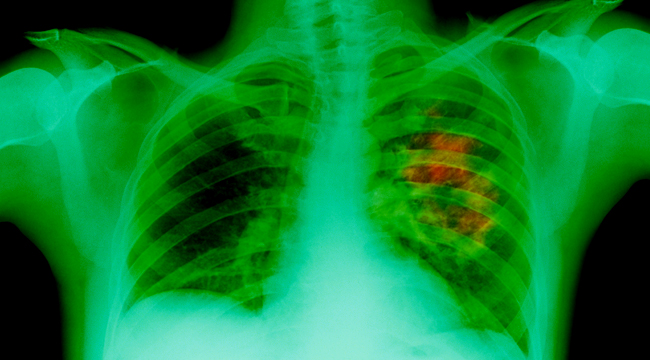

Lung cancer, also known as lung carcinoma, is the second most common type of cancer and is also considered as the leading cause of cancer death in the United States, with more than 150,000 deaths in 2014. The most common cause of lung cancer is cigarette smoking, which is associated with around 80 to 90 percent of lung cancers. Even if you do not smoke, the smoke from other people's cigarettes, pipes, or cigars also causes lung cancer, so being in close proximity with those who do smoke also puts your health in danger.

There are three main types of lung cancer — non-small cell lung cancer, small cell lung cancer, and lung carcinoid tumor. Non-small cell lung cancer is the most common type that accounts for around 85 percent of lung cancers. Small cell lung cancer is also known as oat cell cancer that tends to spread easily, and it accounts for approximately 10 to 15 percent of lung cancers. Lastly, lung carcinoid tumor only comprises less than five percent of lung cancers and it grows slowly and rarely spread.